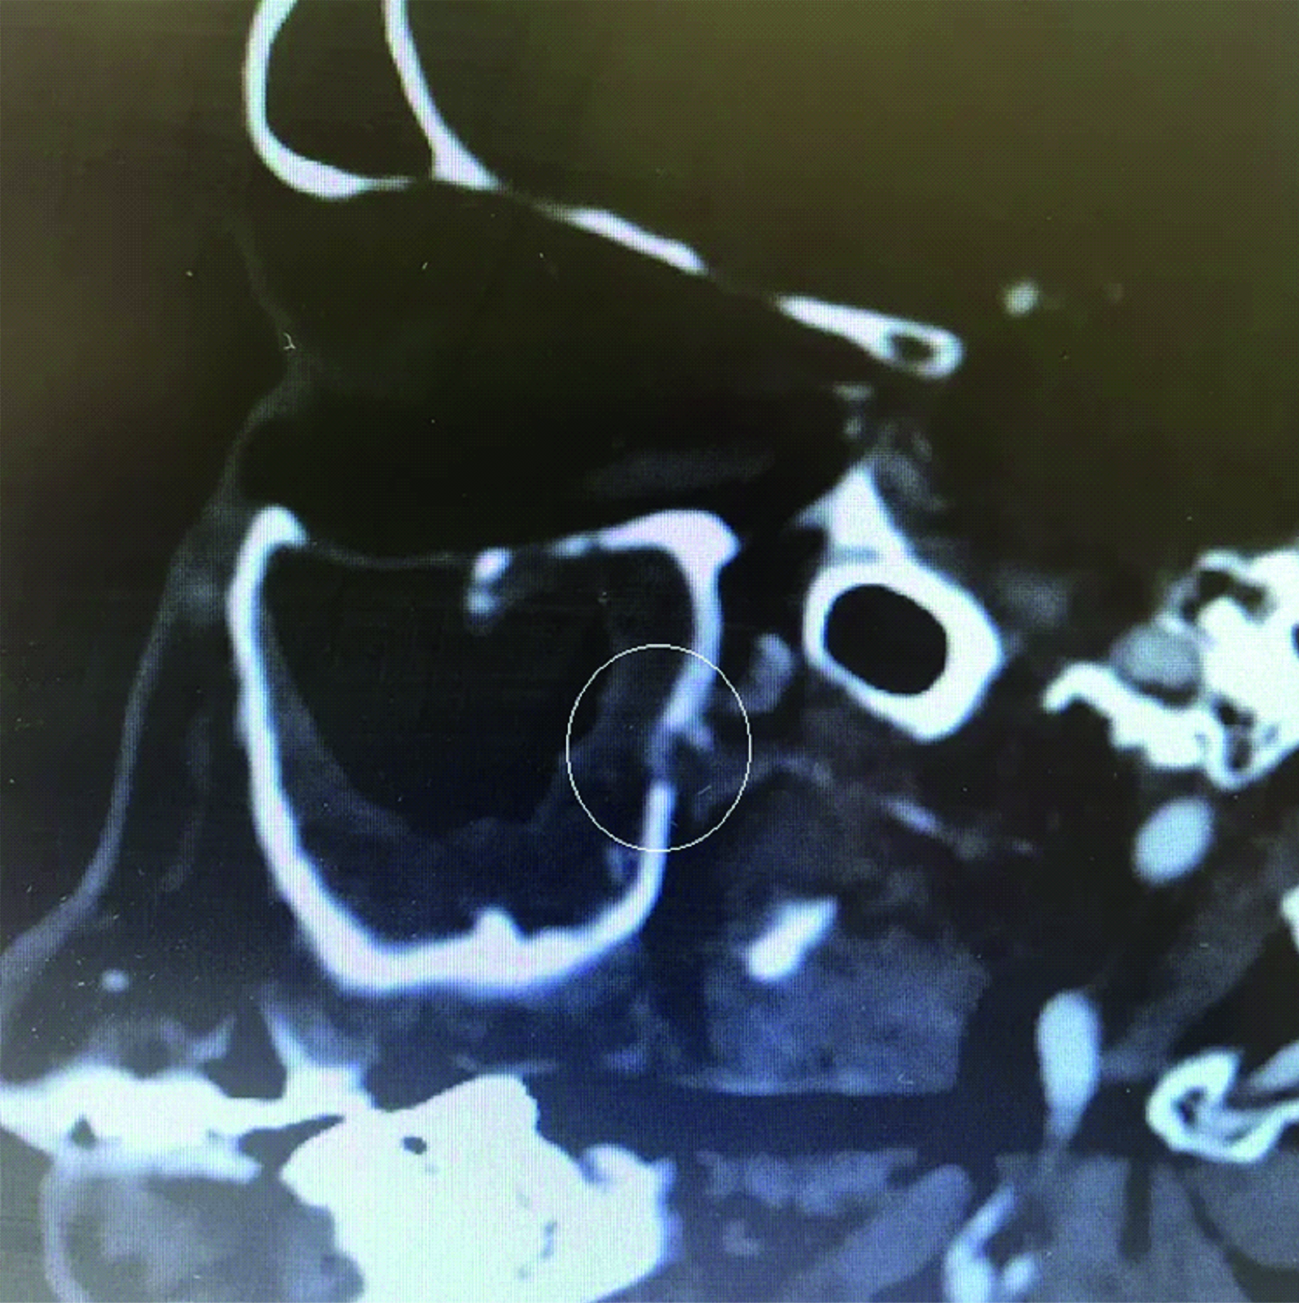

30.03.2016 было выполнено контрольное КТ ОНП в условиях поликлиники для оценки динамики состояния после оперативного вмешательства – визуализирован пристеночный отек верхнечелюстных пазух справа и слева, ярко выражен дефект задней стенки правой верхнечелюстной пазухи (рисунки 2, 3).

Рисунок 2. КТ околоносовых пазух от 30.03.2016. Сохраняется пристеночный отек верхнечелюстной пазухи, костный дефект задней стенки правой верхнечелюстной пазухи.

Figure 2. CT imaging of the paranasal sinuses dated 30.03.2016. The parietal edema of the maxillary sinus persists, as well as a bone defect in the posterior wall of the right maxillary sinus.

Рисунок 3. КТ околоносовых пазух от 30.03.2016. Сагиттальный срез. Ярко выраженный костный дефект задней стенки верхнечелюстной артерии.

Figure 3. CT imaging of the paranasal sinuses dated 30.03.2016. Pronounced bone defect in the posterior wall of the maxillary artery. Sagittal section. Pronounced bone defect in the posterior wall of the maxillary artery.